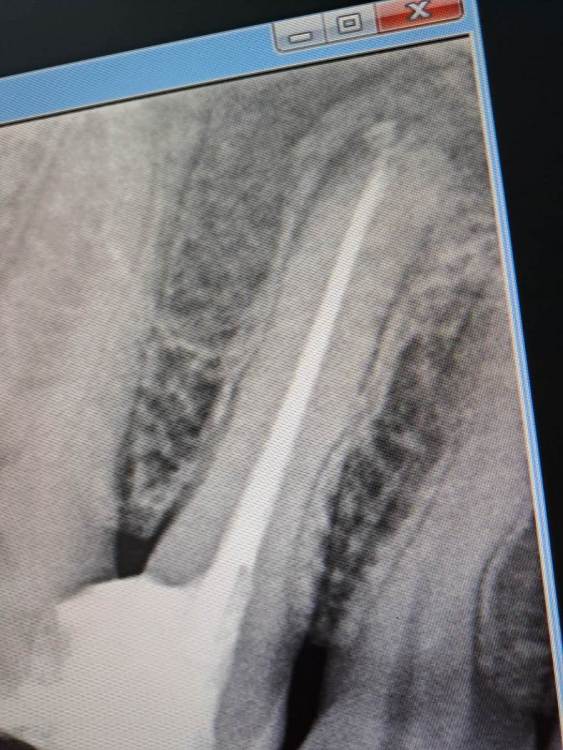

FISSMAN Опубликовано 7 апреля, 2023 Автор Поделиться Опубликовано 7 апреля, 2023 24.03.2023 в 09:20, IvanK сказал: Здравствуйте Если Вы не доверяете своему врачу, то нужно найти врача, которому Вы сможете доверять для ответов на Ваши вопросы нужно больше объективных данных (еще снимки, фото) Доверяю после лечения мне становится легче, хотел узнать про качество. Вот фото после лечения этих зубок Ссылка на комментарий

IvanK Опубликовано 8 апреля, 2023 Поделиться Опубликовано 8 апреля, 2023 выглядит все не плохо для более достоверной оценки нужна компьютерная томография 1 Ссылка на комментарий